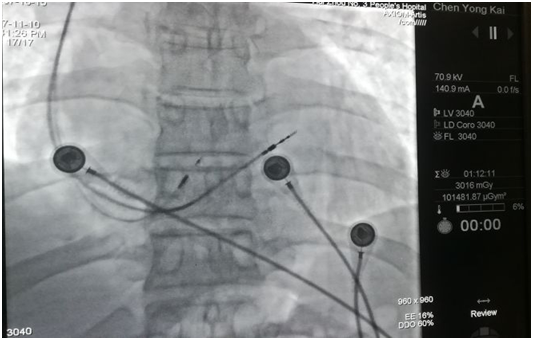

手術(shù)當(dāng)天,楊飛副主任醫(yī)師與鐘思干主任沉著冷靜、有條不紊實(shí)施著手術(shù),首次嘗試就成功穿刺腋靜脈,順利置入血管鞘,沿鞘管送入3830主動(dòng)電極至房室交界處房側(cè),順利找到his電位。

手術(shù)進(jìn)行中

His電極及右室間隔面電極